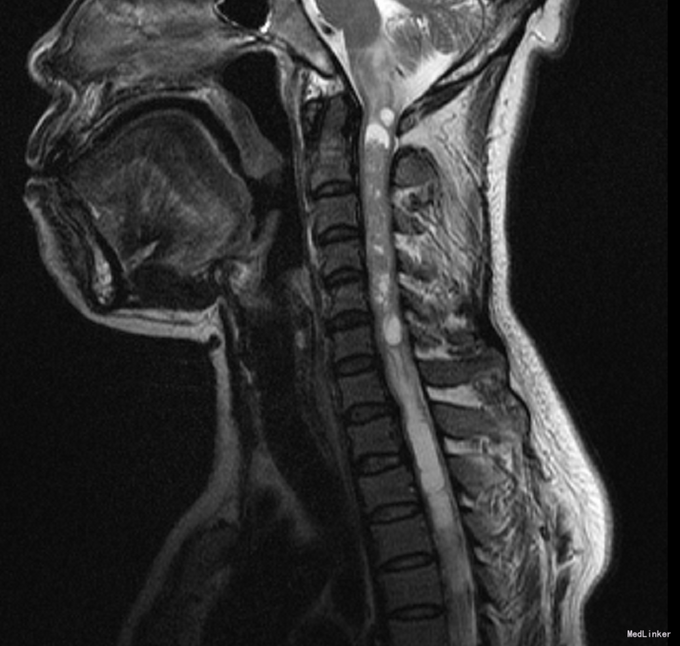

患者,女,50岁,因“左上肢麻木2年余,后颈部疼痛半年余”入院。

四肢自主活动,肌力V级,双上肢浅感觉减退,深感觉正常,病理征阴性。 本院颈椎MRI示“延髓及约颈1-6椎体水平颈髓髓内肿瘤,室管膜瘤可能性大,胶质瘤(毛星)待排。”

初步诊断:脊髓肿瘤。全麻下行[C2-6]脊髓髓内肿瘤切除术,术后给予头孢呋辛针 1.5g ivgtt q8h预防感染及止血、营养神经、补液、对症等治疗。

术后常规病理示:脊髓髓内室管膜瘤。